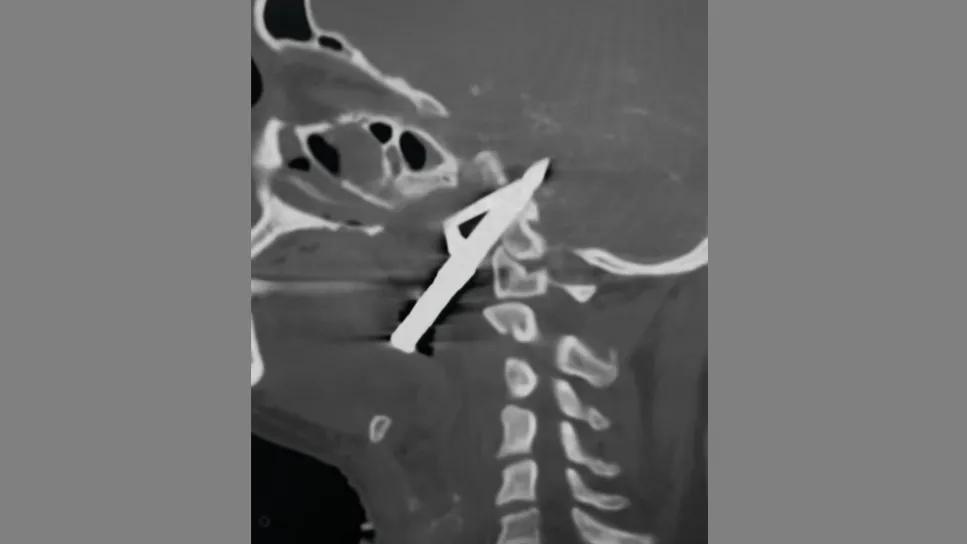

CT scan showing a sharp object penetrating a human brain

With prompt management, even a severe penetrating traumatic brain injury such as a gunshot wound to the head can have a good outcome, according to guidelines unveiled by the Brain Trauma Foundation at the recent annual meeting of the Congress of Neurological Surgeons. These second-edition guidelines, focusing specifically on this highly grave type of injury, are to be published in December in Neurosurgery, nearly 25 years after the first edition.